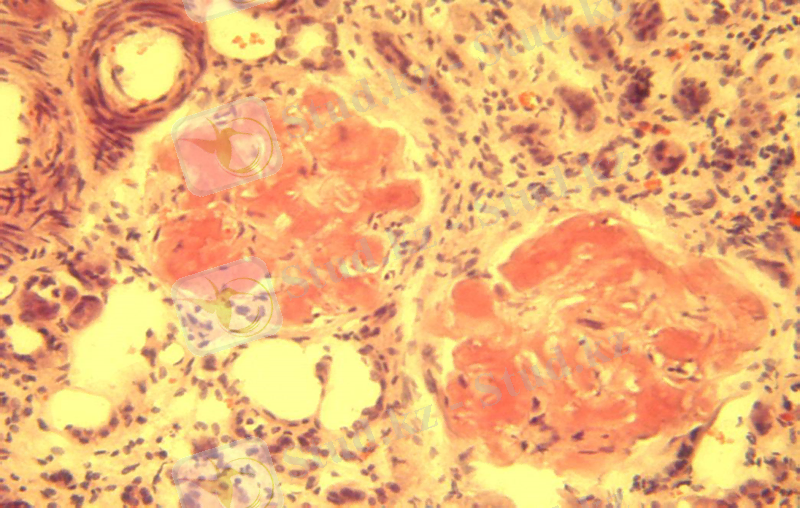

2 сурет. Фибриноидты ісіну

Фибриноидтық ісіну деп негізгі зат пен талшықтардың бүлінуімен, тамыр қабырғасы өткізгіштігінің күрт күшеюімен, фибриноидтың түзілуімен сипатталатын дәнекер ұлпаның терең, қайтымсыз зақымдалуын айтады.

Фибриноид күрделі зат. Құрамында белок, полисахарид, ыдыраған дәнекер ұлпа, қан плазмасының белоктары бар.

Микрокөрінісі: коллаген талшықтарының бумалары гомогенденеді, қалыңдайды, бір-бірімен қосылады. Талшықтық құрылымы жойылады. Пиронин бояуымен қызыл түске қанық боялады. Мүшенің сыртқы көрінісі өзгермейді.

Себептері: инфекиялық және аллергиялық аурулар.

Ақыры: фибриноидты некрозға жалғасады. Соңынан гиалинозға ұшырайды.

Организмге әсері: мүше қызметі бұзылады.